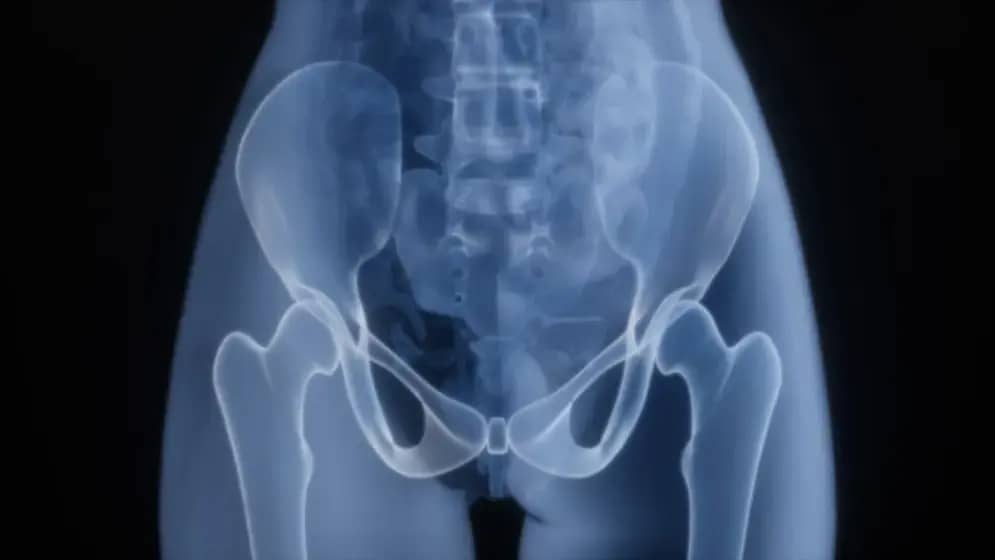

Prosečna težina prostate kod odraslog muškarca iznosi oko 30 grama, pa masa uklonjenog benignog tumora dodatno svjedoči o vrhunskoj izvedbi zahvata. Uvećana prostata predstavlja najčešći zdravstveni problem kod muškaraca starijih od 50 godina, a ovaj slučaj ekstremnog uvećanja zahtijevao je izuzetnu hiruršku preciznost. Uspjeh tima užičkih urologa pokazuje da su složene operacije u oblasti urologije moguće i van većih centara, te potvrđuje značaj dobro obučenog urologijskog tima i kvalitetne javne zdravstvene zaštite u regionu.